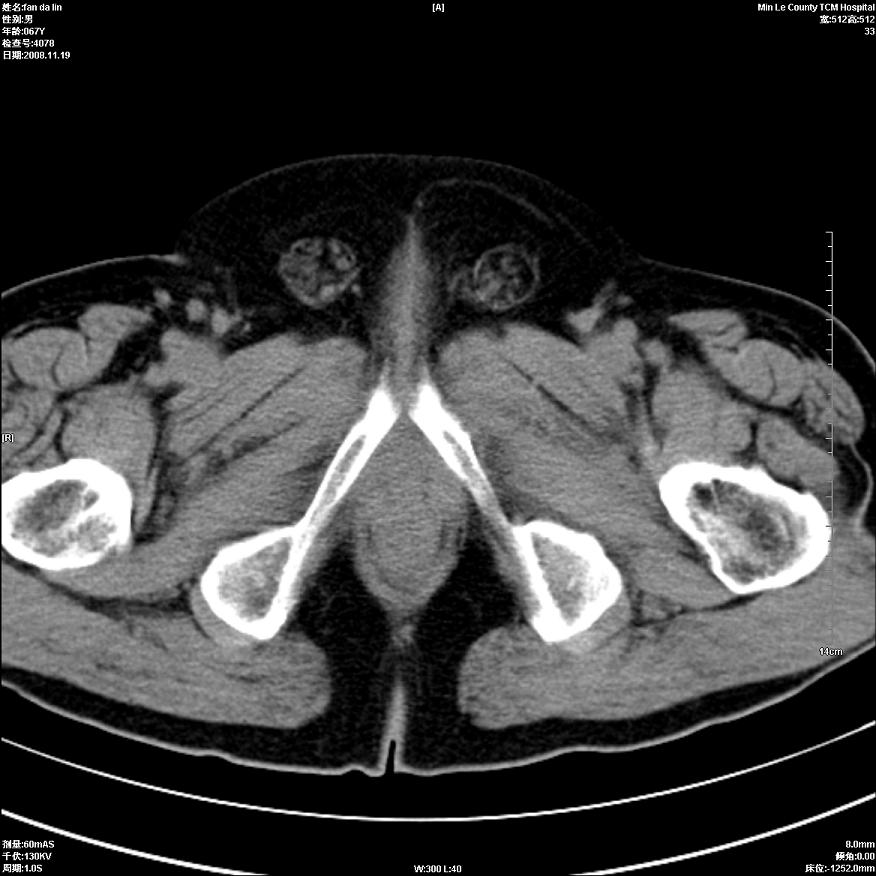

标题: CT16698:M67Y,看看直肠下端是不是病变 [打印本页]

标题: CT16698:M67Y,看看直肠下端是不是病变

粘膜皱壁,不除外内痔

直肠及乙状结肠管壁均增厚,考虑炎症.

直乙交界处肠壁不规则增厚,还是做个肠镜吧

只是肠壁局限性增厚,但难说明问题。